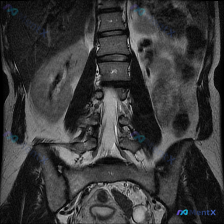

整理了一份影像分析资料,情况有点意思: 用户是因为怀疑脊柱侧弯去做的检查,拿到的是腰椎MRI(T1加权像,冠状位)。 先不说结论,这份影像里的几个点先放出来: 1. 腰椎序列在冠状面上排列基本规整,各椎体高度、信号均匀 2. 未见明显的侧弯弧度、椎体破坏或巨大软组织肿块 3. 椎间隙、椎间孔、小关节...

网上看到一份病例资料,本来是因为怀疑“脊柱侧弯(Scoliosis)”去做的检查,结果腰椎MRI拍出来,第一眼的重点反而不在侧弯上。 先看这张T1加权冠状位的核心表现: 1. 关于侧弯:腰椎生理曲度尚可,未见明显侧弯畸形,椎体序列基本对齐——可以说直接排除了结构性侧弯的可能。 2. 真正的红旗征象:...

整理到一张腰椎MRI的冠状位T1WI图像,先不说结论,大家第一眼会怎么看? 目前能看到的影像表现: - 腰椎明显向右侧凸,有椎体旋转和倾斜 - 两侧椎间隙高度不均匀,部分变窄 - 多个椎间盘信号降低 - 椎体骨髓信号基本是弥漫中等偏高,没看到明确的局灶骨质破坏或大肿块 - 两侧腰大肌形态不对称 这份...

整理到一份腰椎MRI T1加权像冠状位的影像分析资料,先不说最终倾向,把核心发现放出来大家讨论下: 核心影像表现: 1. 脊柱:明显腰椎右侧凸畸形,椎体边缘骨质增生、部分模糊,椎间隙左右不对称、部分狭窄,椎间盘T1信号广泛减低;小关节间隙窄、关节突肥大,凹侧结构紊乱。 2. 骨髓信号:关键! 椎体骨...